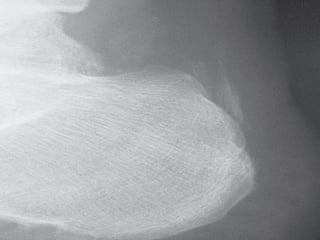

Plain Radiographs

:

Chondrocalcinosis It is classically seen in

-

Fibrocartilage (knee menisci, triangular

ligament of the wrist, symphysis pubis) →

punctate

Hyaline articular cartilage (knee, shoulder,

hip) → linear

linear

Tendon insertion sites (Achilles) → linear

Structural Joint Changes

CPPD can be associated with

subchondral sclerosis, subchondral

cyst, and joint space narrowing. Although

the findings are also seen in OA, the

location may help differentiate

.

Unlike RA, CPPD does not have typical

bony erosions

IMAGING Plain Radiographs : Chondrocalcinosis Itis classically seen in - Fibrocartilage (knee menisci, triangular ligament of the wrist, symphysis pubis) → punctate punctate - Hyaline articular cartilage (knee, shoulder, hip) → linear linear - Tendon insertion sites (Achilles) → linear - Bursa

Structural Joint Changes - CPPDcan be associated with subchondral sclerosis, subchondral cyst, and joint space narrowing. Although the findings are also seen in OA, the location may help differentiate . - Unlike RA, CPPD does not have typical bony erosions .